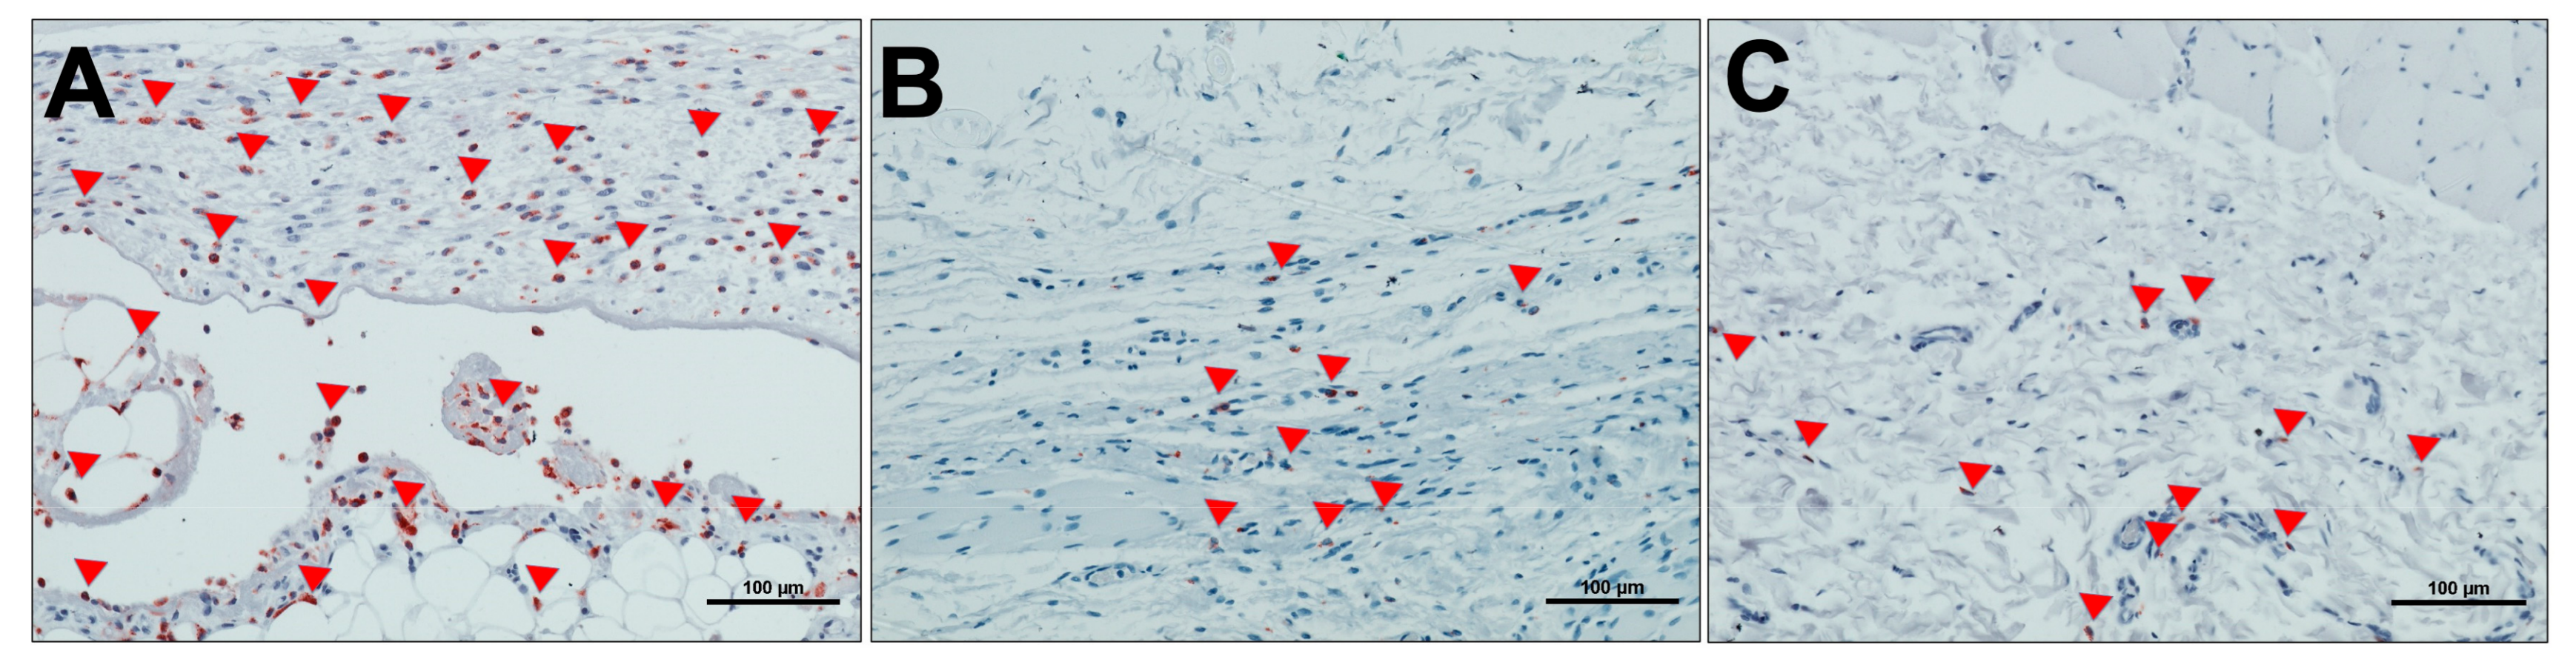

Qualitative Analysis of Cellular Reaction to MM over the Study Period

3.3.2. Evaluation of the Total Amount of CD-68-Positive Mononuclear Cells

3.3.3. Evaluation of Total Amount of Multinucleated Giant Cells (MNGCs)

3.3.4. Evaluation of Implantation Site Vascularization